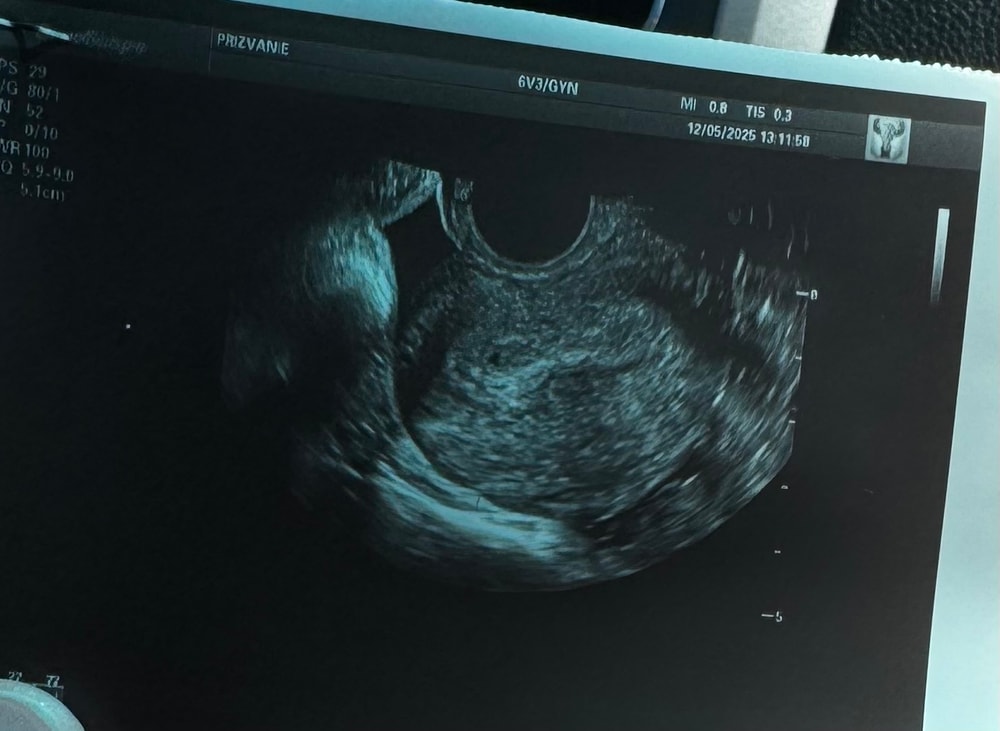

SLIVKA, была за день до сдачи ХГЧ

Обнаружили плодное яйцо)

РЕКА, на узи увидели одно плодное яйцо непонятной мне формы

Но в роду у меня много двоен, было бы здорово

Алиса , а сколько желтых тел? У меня похожие цифры хгч, 2 желтых тела. Сколько плодных яиц сейчас сложно посчитать.

РЕКА, попала на прием к первому попавшемуся узисту, она мне ни слова не сказала про желтое тело, как и про плодное яйцо неправильной формы. Переделаю узи через неделю, наверное